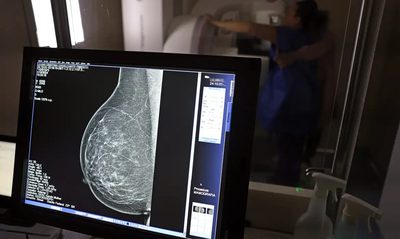

Ampliação de Mamografia

Recentemente o Ministério da Saúde anunciou mudança na faixa etária para realização da mamografia no SUS. A partir de agora o exame está disponível também para mulheres a partir dos 40 anos, mesmo na ausência de sintomas de câncer. A ampliação da faixa etária fortalece o diagnóstico precoce e o acesso à assistência, especialmente para mulheres que antes encontravam barreiras no sistema público de saúde, como a exigência de histórico familiar ou de sinais clínicos da doença. Em 2024, as mamografias realizadas em mulheres com menos de 50 anos já corresponderam a 30% do total, ultrapassando 1 milhão de exames.